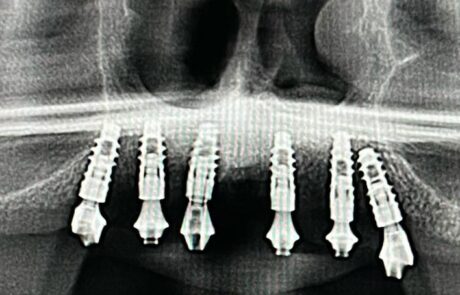

Implantología Bucomaxilofacial

Corona sobre implantes o piezas dentales

Puentes sobre implantes o piezas dentarias